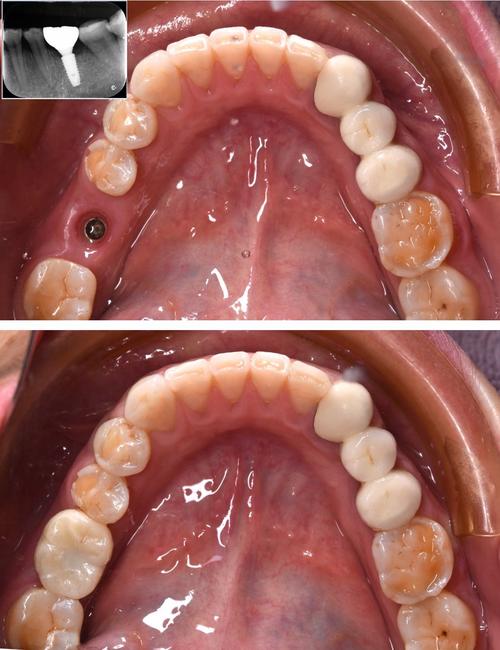

- 备洞与植入:根据种植导板,依次使用不同直径的备洞钻逐级扩大骨孔,将3i植体旋入骨内,确保种植体顶端与牙槽骨平面平齐或位于骨下0.5-1mm(利于软组织美学)。

- 缝合与愈合:用可吸收缝线缝合牙龈,术后拍摄X光片确认种植体位置。

- 牙冠佩戴:试戴牙冠,调整咬合与颜色,最终粘固或螺丝固位,完成修复。